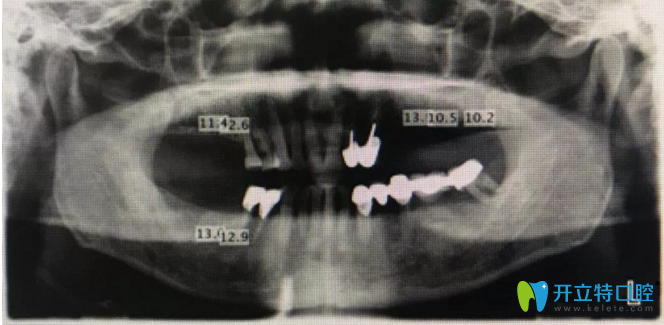

患者資料:17,16,24,25,26,27,47,46缺失3年余,原活動(dòng)義齒使用不適,咨詢重新制作義齒。口內(nèi)檢查缺牙區(qū)牙槽嵴寬度8~10mm,X光檢查,測(cè)量骨高度如下所示,非常適合種植修復(fù)。

下為術(shù)前X光片